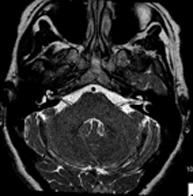

- IAC MRI

This non-invasive diagnostic procedure uses an electromagnetic field and radio waves (from a transmitter and receiver) to acquire high-definition anatomical images of the internal auditory canal (IAC). It is a radiation-free procedure. Indicated for: hearing problems, dizziness, vertigo.